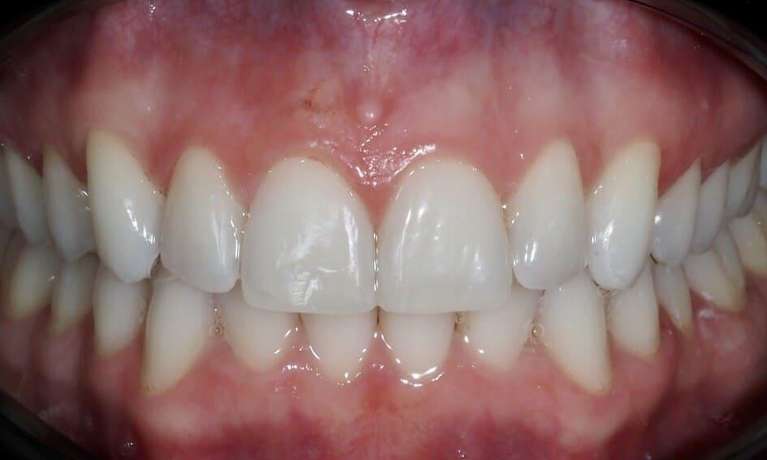

This patient was worried about the incisal edges of her front teeth that had become thin and prone to chipping. This had started in her twenties and unfortunately, now in her thirties, was progressing due to her deep and tight bite and minor crowding.

In her case, Dr Gourlay used 14 series of Invisalign aligners over 14 weeks to align her teeth into a more protected bite pattern. She then used composite bonding to restore the chipped edges. The patient has since moved on to using retainers at night to maintain and protect the position of the teeth.